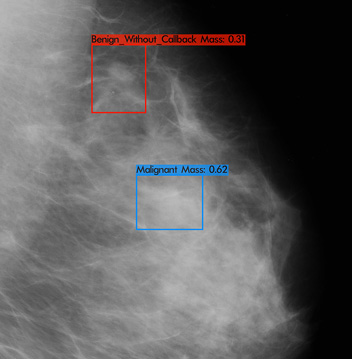

RADIFY® for Breast Imaging

RADIFY® for mammography assists radiologists in the diagnosis and screening of breast lesions. Mammography has been the frontline screening tool for breast cancer for decades. The early detection of breast cancer is life-saving especially in under resourced countries. RADIFY® have developed RADIFY® for mammograms as a clinical decision support tool for radiologists when screening for breast cancer. .